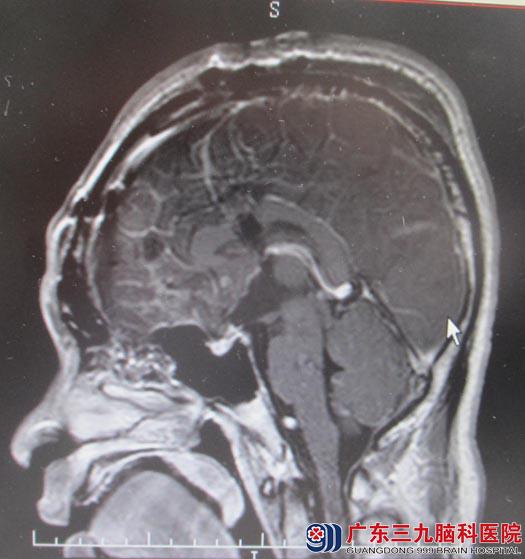

入住广东三九脑科医院综合神经外科,鲁明主任主刀急诊全麻下行经额胼胝体及前纵裂联合入路鞍区颅咽管瘤切除术。由于肿瘤为囊实性,从鞍区往三脑室方向生长,术中按经胼胝体入路作右侧额部弧形切口,铣刀取下4cm×5cm骨瓣,从纵裂逐步分离,切除肿瘤,90%的肿瘤组织顺利切除,但剩余10%的肿瘤与垂体柄粘连紧密,手术视野受限,为能全切肿瘤,术中果断延长手术切口,于右侧额部另铣一骨瓣,从前纵裂终板入路切除剩余肿瘤。最终肿瘤镜下全切,术后复查头颅MR未见肿瘤残留。术后小舟恢复良好,四肢活动正常,未出现异常并发症。

▲手术后